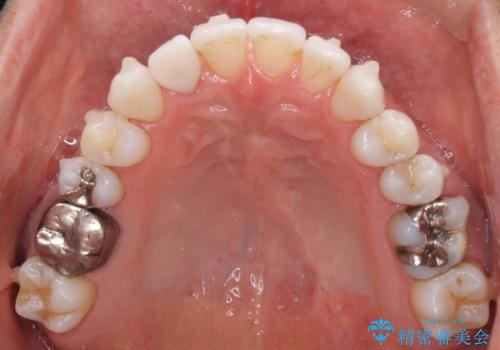

- 治療途中の前歯と上下前歯のデコボコ気にして来院された患者様です。

前歯のデコボコはインビザラインにより歯列を整え、その後に、前歯などをオーダーメイドタイプのオールセラミッククラウンにて補綴治療することとしました。

長時間のマウスピース装着に協力いただき、短期間で歯列をしっかりと改善することができました。

ホームホワイトニングを併用していただいたので、とても明るい口元に仕上がり、患者様には大変満足していただきました。